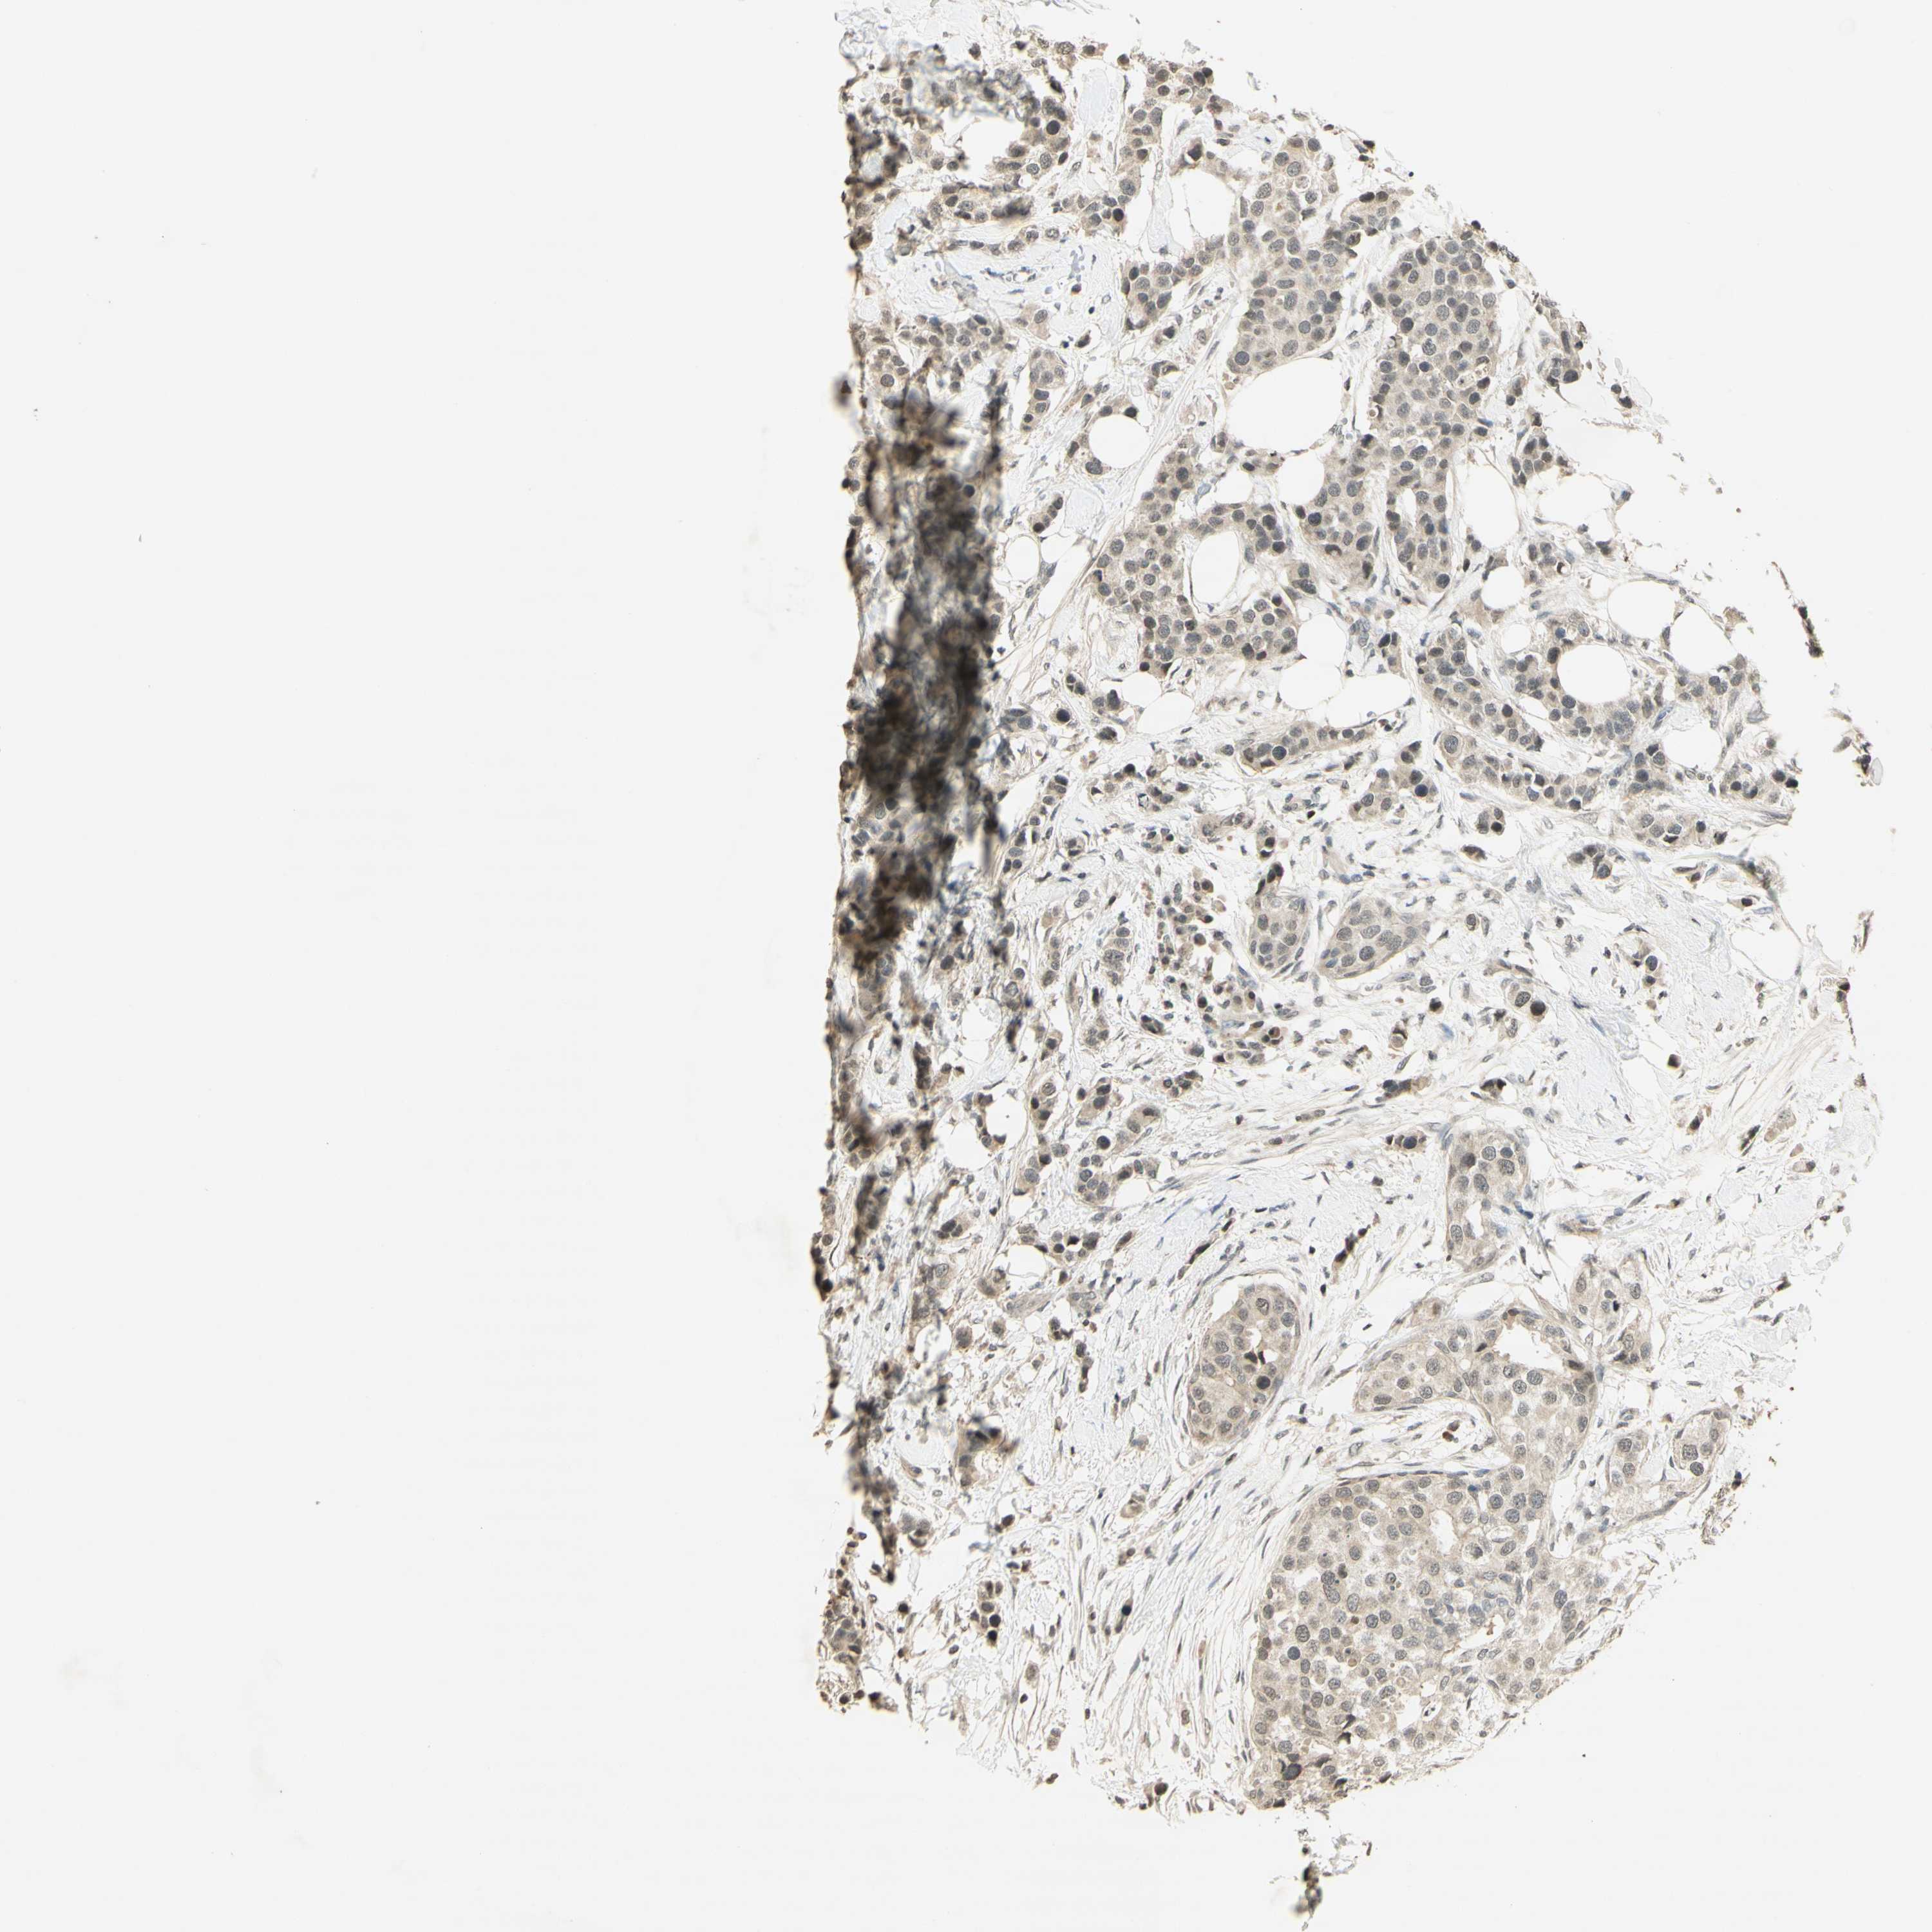

CANCER BREAST CANCER Show tissue menu

BRCA TCGA BRCA VALIDATION PROTEIN EXPRESSION

ANTIBODIES

AND

VALIDATION